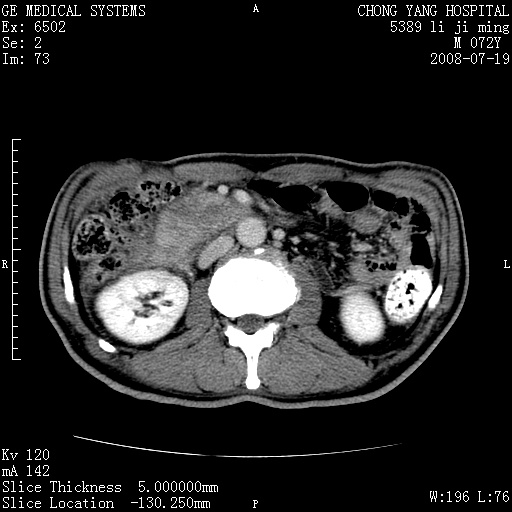

以下是引用zjzjr在2008-7-19 20:57:00的发言:[br]胰头增大,边缘模糊,周围可见渗出影,右侧肾前筋膜增厚.支持胰腺炎.

以下是引用不学无术在2008-7-19 23:15:00的发言:[br]胰腺增大尤以胰头明显,边缘模糊,周围可见渗出影,右侧肾前筋膜增厚,肠管於涨.支持胰腺炎